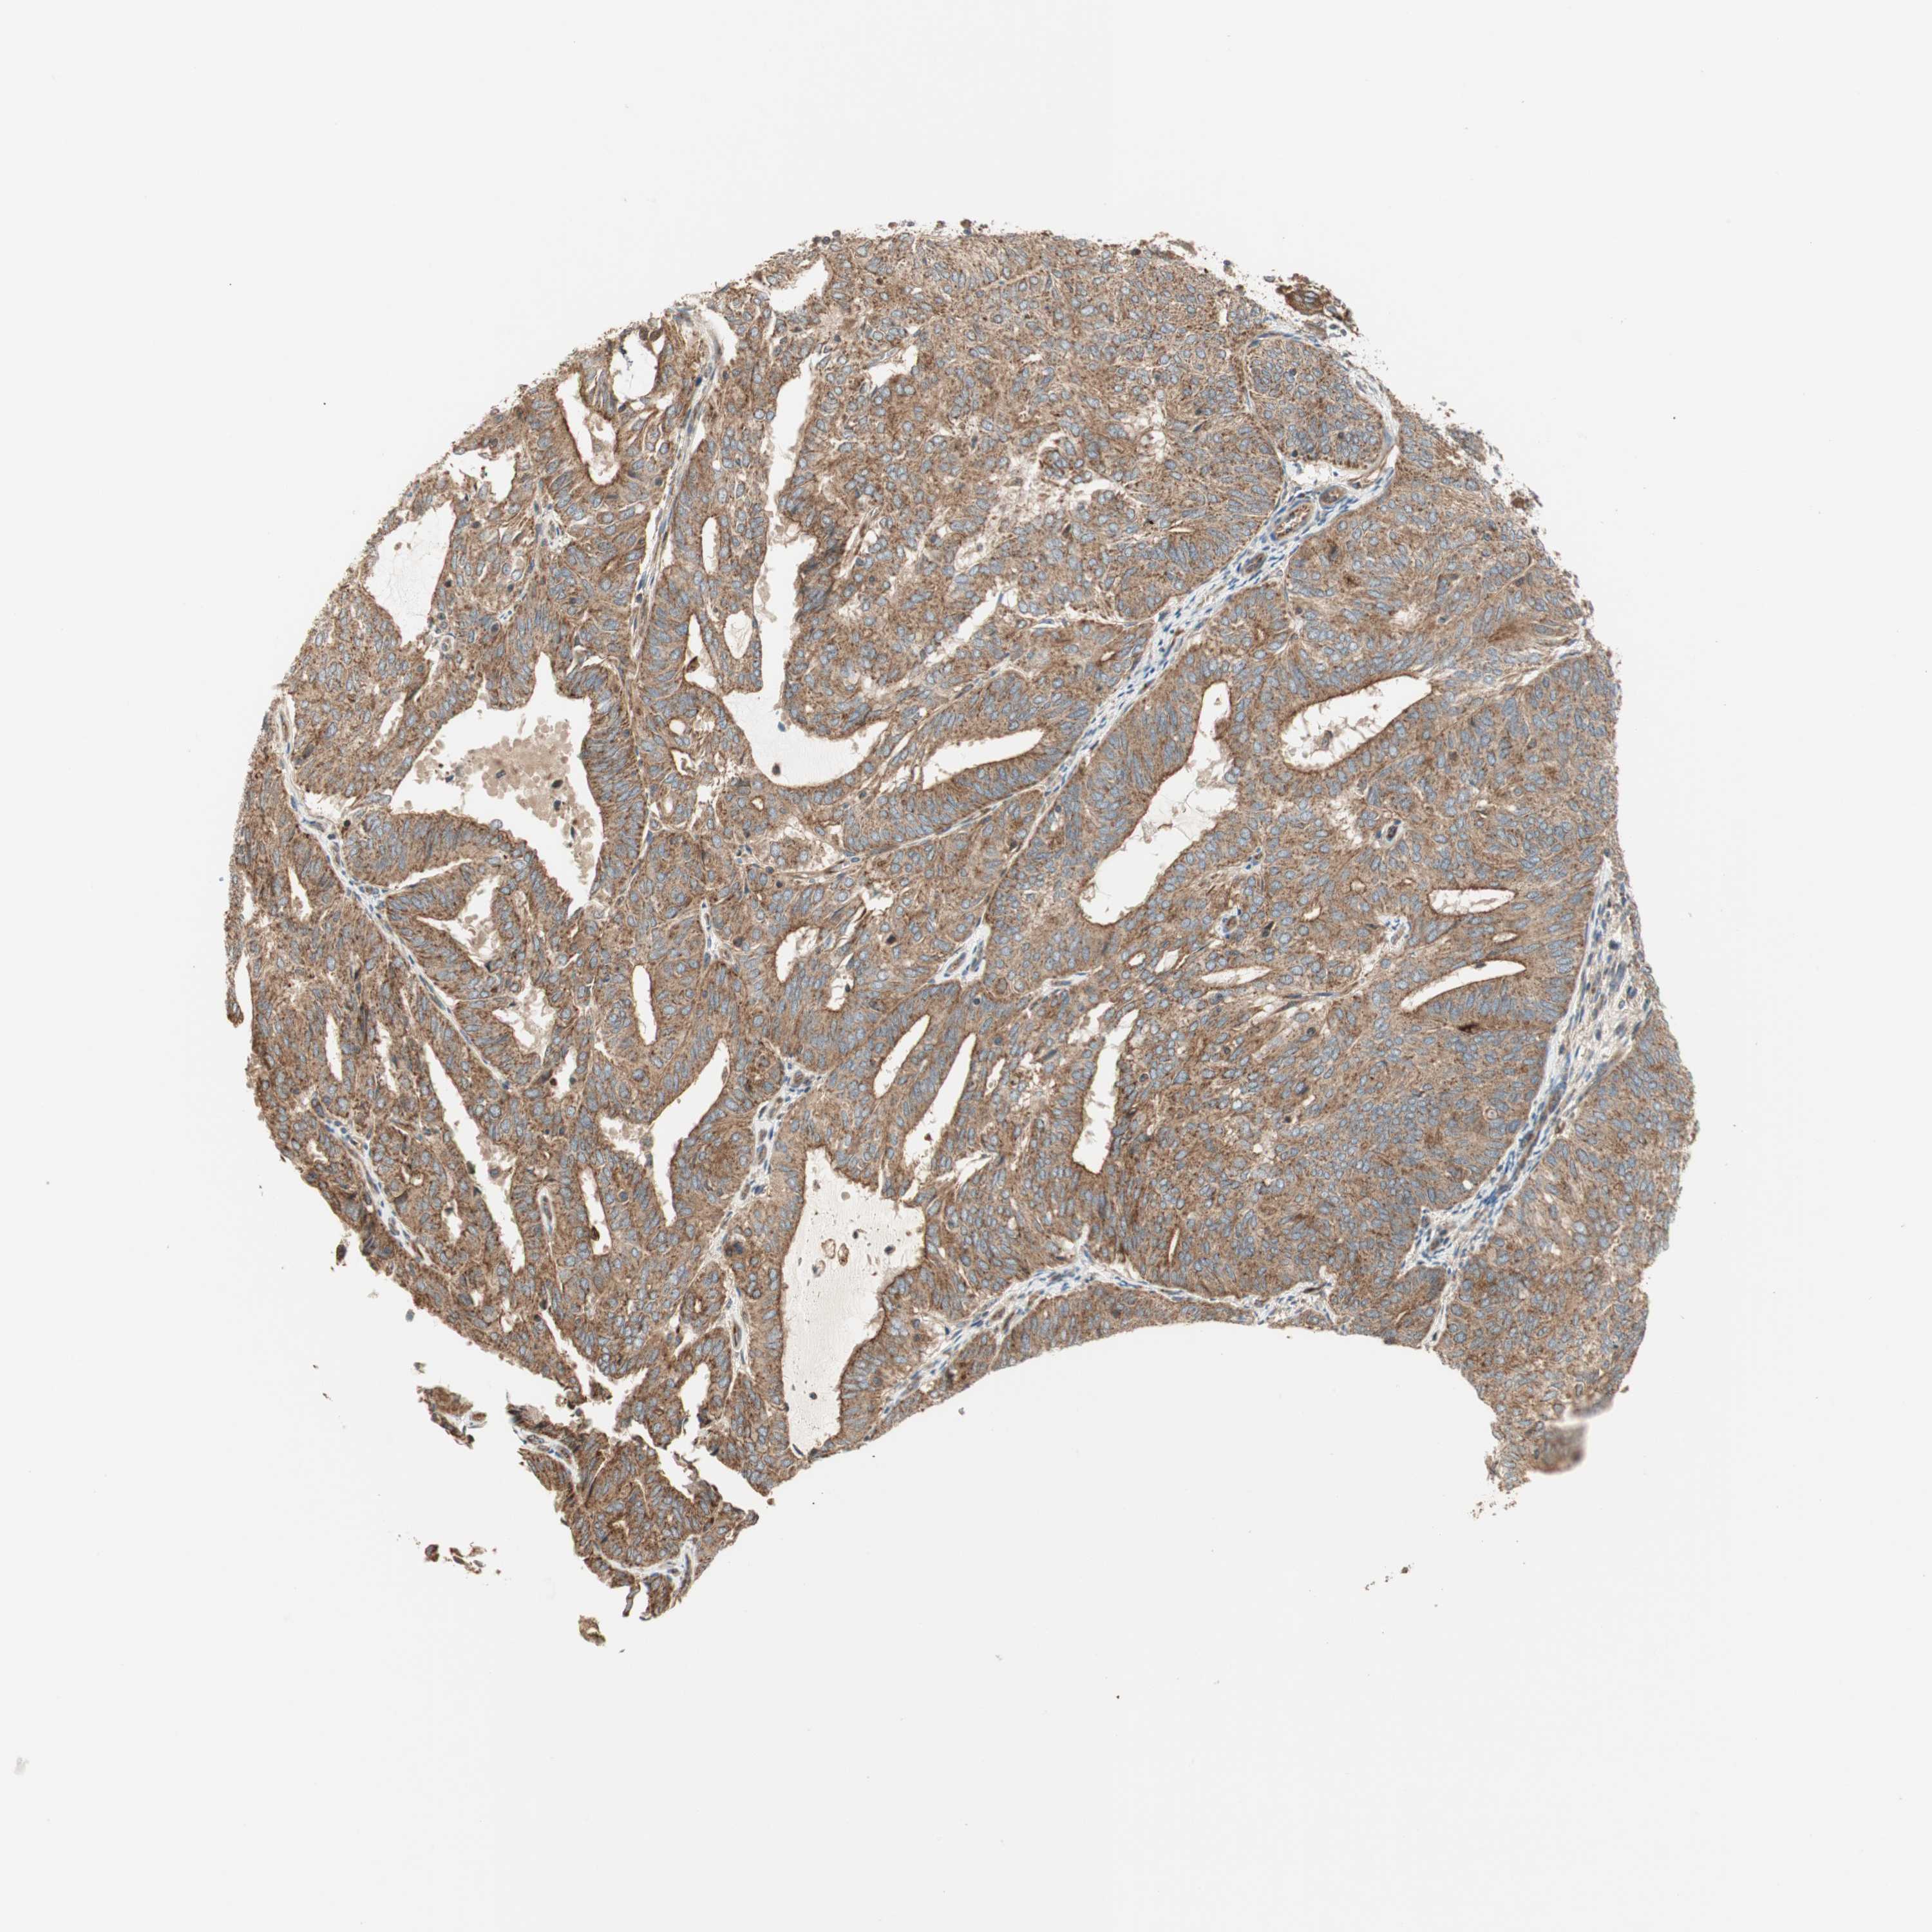

ENDOMETRIAL CANCER - Protein expressioni

A mouse-over function shows sample information and annotation data. Click on an image to view it in a full screen mode. Samples can be filtered based on level of antibody staining by selecting one or several of the following categories: high, medium, low and not detected. The assay and annotation is described here.

Note that samples used for immunohistochemistry by the Human Protein Atlas do not correspond to samples in the TCGA dataset.

Antibody stainingi

Antibody staining in the annotated cell types in the current human tissue is reported as not detected, low, medium, or high, based on conventional immunohistochemistry profiling in selected tissues. This score is based on the combination of the staining intensity and fraction of stained cells.

Each image is clickable and will lead to virtual microscopy that enables deeper exploration of all samples and also displays staining intensity scores, fraction scores and subcellular localization as well as patient and tissue information for each sample.

Antibody HPA007301

Staining

High

Medium

Low

Not detected

Intensity

Strong

Moderate

Weak

Negative

Quantity

>75%

75%-25%

<25%

None

Location

Nuclear

Cytoplasmic/membranous

Cytoplasmic/membranous,nuclear

Adenocarcinoma, NOS